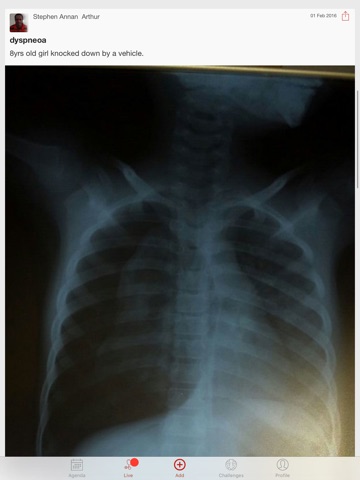

Cardiology Rounds is an exclusive app for Cardiologists get daily journal updates and share cases.